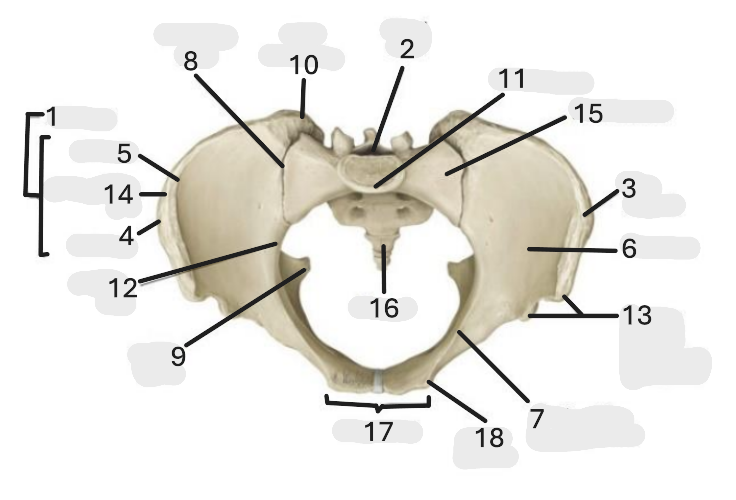

Where is the iliac crest

1

where is the sacral canal

2

Where is the iliac tubercle

3

Where is the outer lip

4

Where is the inner lip

5

Where is the iliac fossa

6

Where is the pectineal line (pecten pubis)

7

Where is the sacroiliac joint

8

Where is the ischial spine

9

Where is the iliac tuberosity

10

Where is the promontory

11

Where is the arcuate line

12

Where is the anterior superior and inferior iliac spine

13

Where is the intermediate line

14

Where is the ala of the sacrum

15

Where is the coccyx

16

Where is the pubic crest

17

Where is the pubic tubercle

18